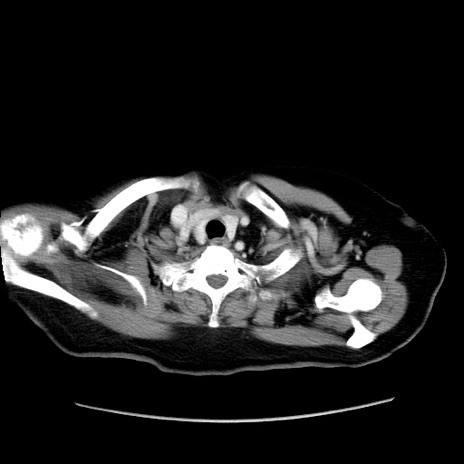

症例19(横断像)

【症例】80歳代女性

【主訴】下腹部痛

【現病歴】約8時間前より下腹部痛の出現あり、救急外来受診。

【既往歴】両側付属器切除

【身体所見】意識清明、下腹部正中に手術痕あり、その部位に一致して圧痛と反跳痛あり。腸蠕動音は亢進。

【データ】WBC 9300、CRP 0.15